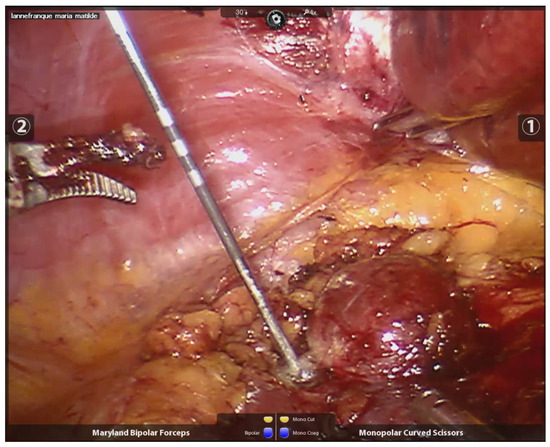

The needle length and diameter were selected based on the size of the tumor and its proximity to or distance from the abdominal wall. The radiofrequency needles had diameters ranging from 1.5 to 3 cm and lengths between 30 and 35 cm. Peri-tumoral radiofrequency needle punctures were performed until maximum impedance was reached, in larger lesions (600–700 kHz), or up to 300–400 kHz, in smaller lesions. The puncture was made 3 mm from the visible tumor edge and 1 to 1.5 cm deep. The needle was not removed until no further evidence of bleeding was observed. The number of punctures varied, depending on the size of the lesion, with all punctures performed peri-tumorally at the border between the tumor tissue and healthy kidney tissue (See Figure 2). After performing radiofrequency along the entire edge of the lesion, a necrotic halo is demarcated, which facilitates its resection (See Figure 3).

Figure 2.

Peritumoral needle positioning and peritumoral radiofrequency.